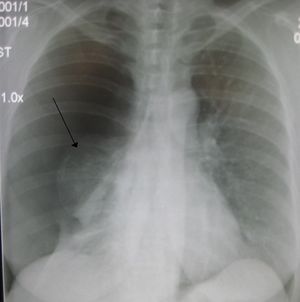

| Right sided spontaneous pneumothorax. An arrow indicating the edge of the collapsed lung. | |